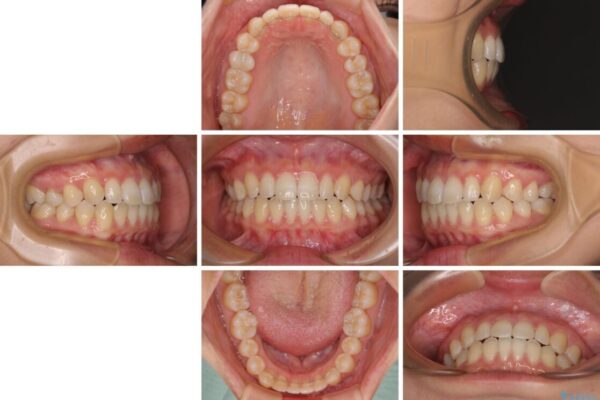

治療前

• 隙間だらけの歯列 インビザラインで改善 治療前画像